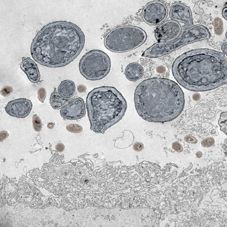

Haut-Rekonstrukt, infiziert mit Laktobazillen (braun) und Candida (blau)